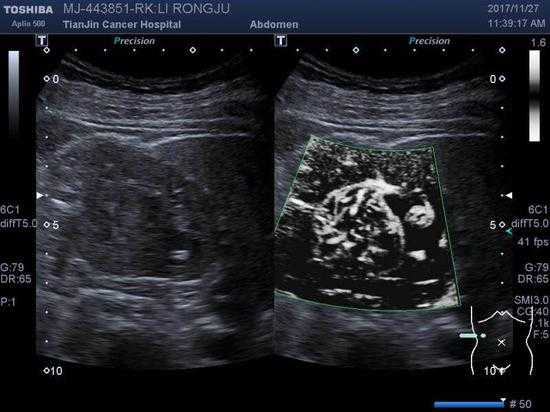

先说说啥是肿瘤成像技术吧。简单讲,它就是通过各种高科技手段,比如X光、超声波、CT扫描这些,把身体里的肿瘤给“拍”出来,让医生看得清清楚楚。这可不仅仅是拍个照片那么简单,它能显示肿瘤的大小、位置、甚至有没有扩散,帮医生制定精准的治疗方案。你知道吗?早期肿瘤可能只有米粒那么大,普通检查根本发现不了,但肿瘤成像技术就能把它揪出来,避免了误诊漏诊的麻烦。这第一次提到肿瘤成像技术,重点就在它能解决早期检测的痛点,让咱们不再因为发现晚而束手无策。

再往下聊,肿瘤成像技术还有更多门道呢。比如说,现在常用的MRI(磁共振成像)和PET-CT(正电子发射断层扫描),这些高级货能提供更详细的图像,连肿瘤的代谢活动都能看出来。俺有个朋友在医院工作,他常念叨:“这些技术真是神了,能分清良性和恶性,避免白挨一刀!”这话不假,以前很多肿瘤得靠手术活检才能确定性质,现在通过成像技术就能初步判断,减少了患者的痛苦和风险。这第二次提到肿瘤成像技术,带来了新的信息:它不仅能检测,还能帮助准确诊断,解决治疗选择上的困惑。情绪化点说,这简直就是给患者吃了颗定心丸,不用再提心吊胆地猜来猜去。